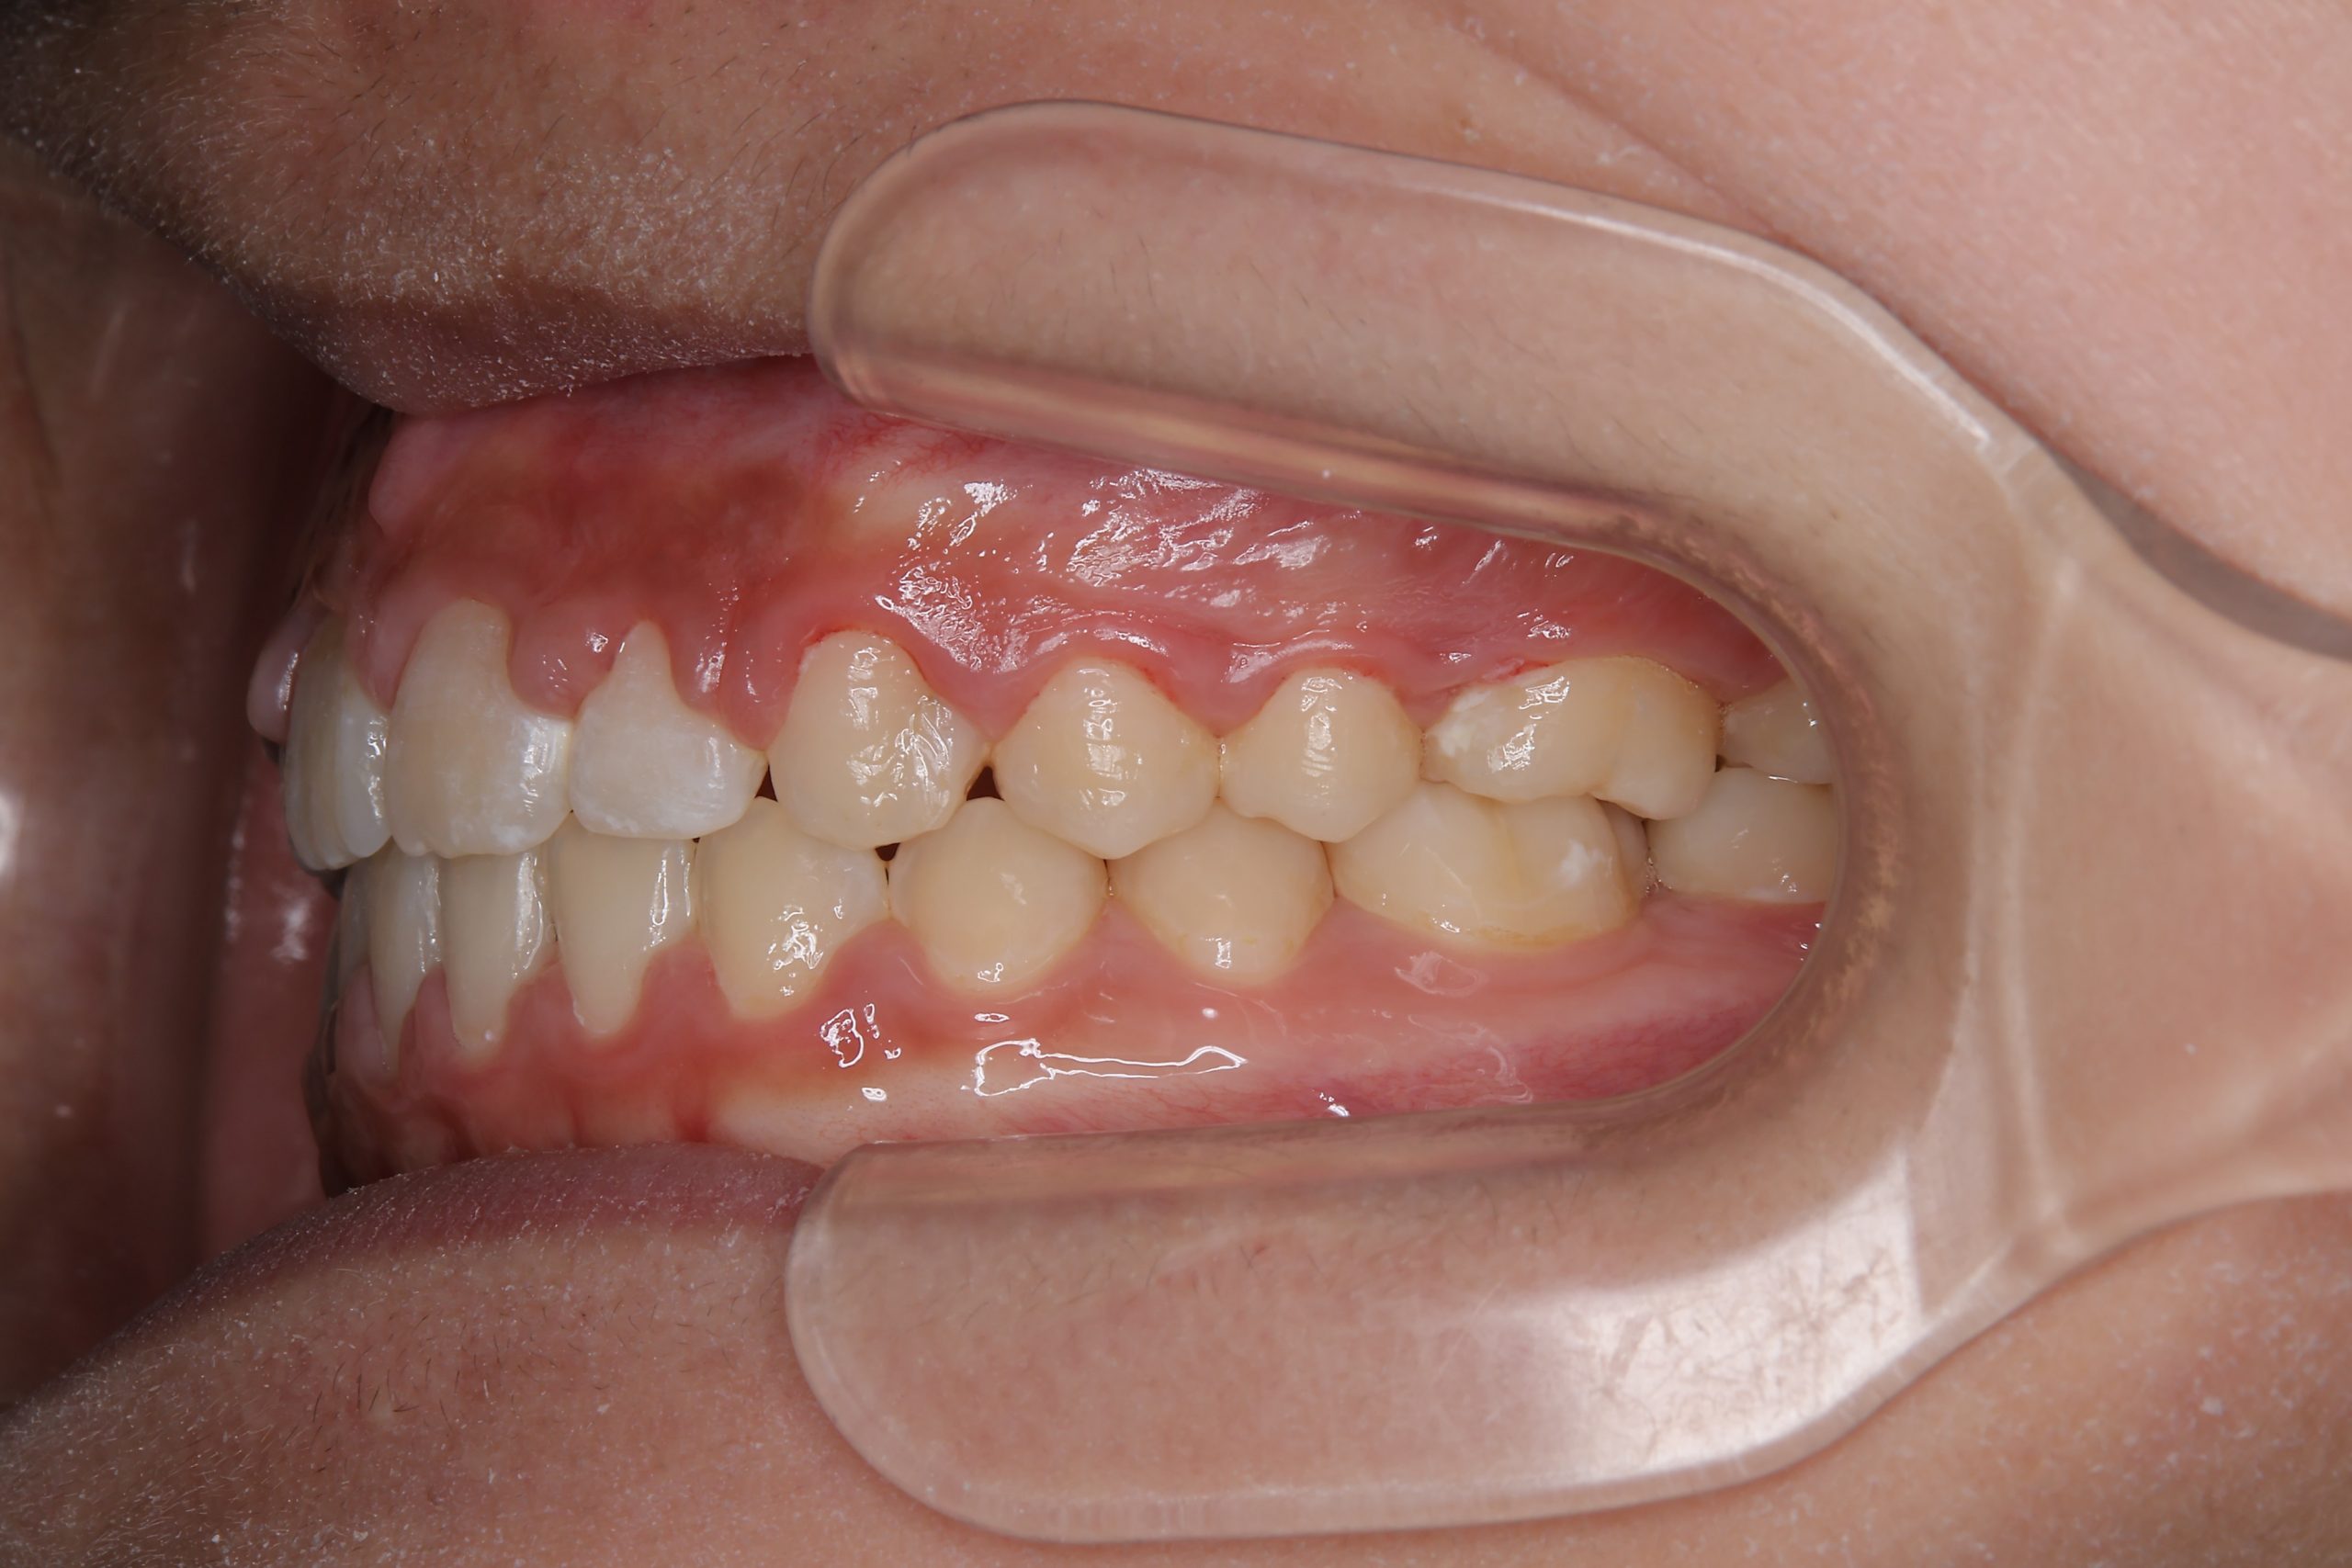

ビフォー

主訴 上前歯が出ている|よく口が開いている

施術内容 上顎急速拡大装置と下顎リンガルアーチを用いて上下顎骨を拡大した。

その後マルチブラケット装置を用いて

非抜歯で歯牙を配列し良好な咬合を獲得した。

鼻閉症状は改善した。

治癒期間 2年10か月間